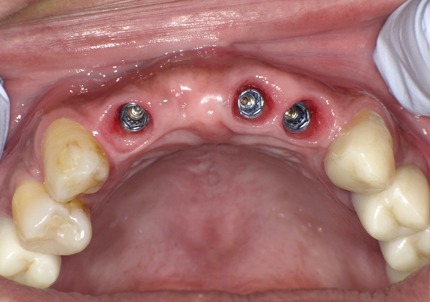

7.サージカルガイドによるインプラント埋入手術

8.テンポラリーヒーリングアバットメント装着して仮歯の作製

➡テンポラリーヒーリングアバットメントとは・・・インプラント手術後、歯ぐき(軟組織)が治癒し、最終的な人工歯が装着されるまでの間、インプラントに装着される一時的な土台のこと